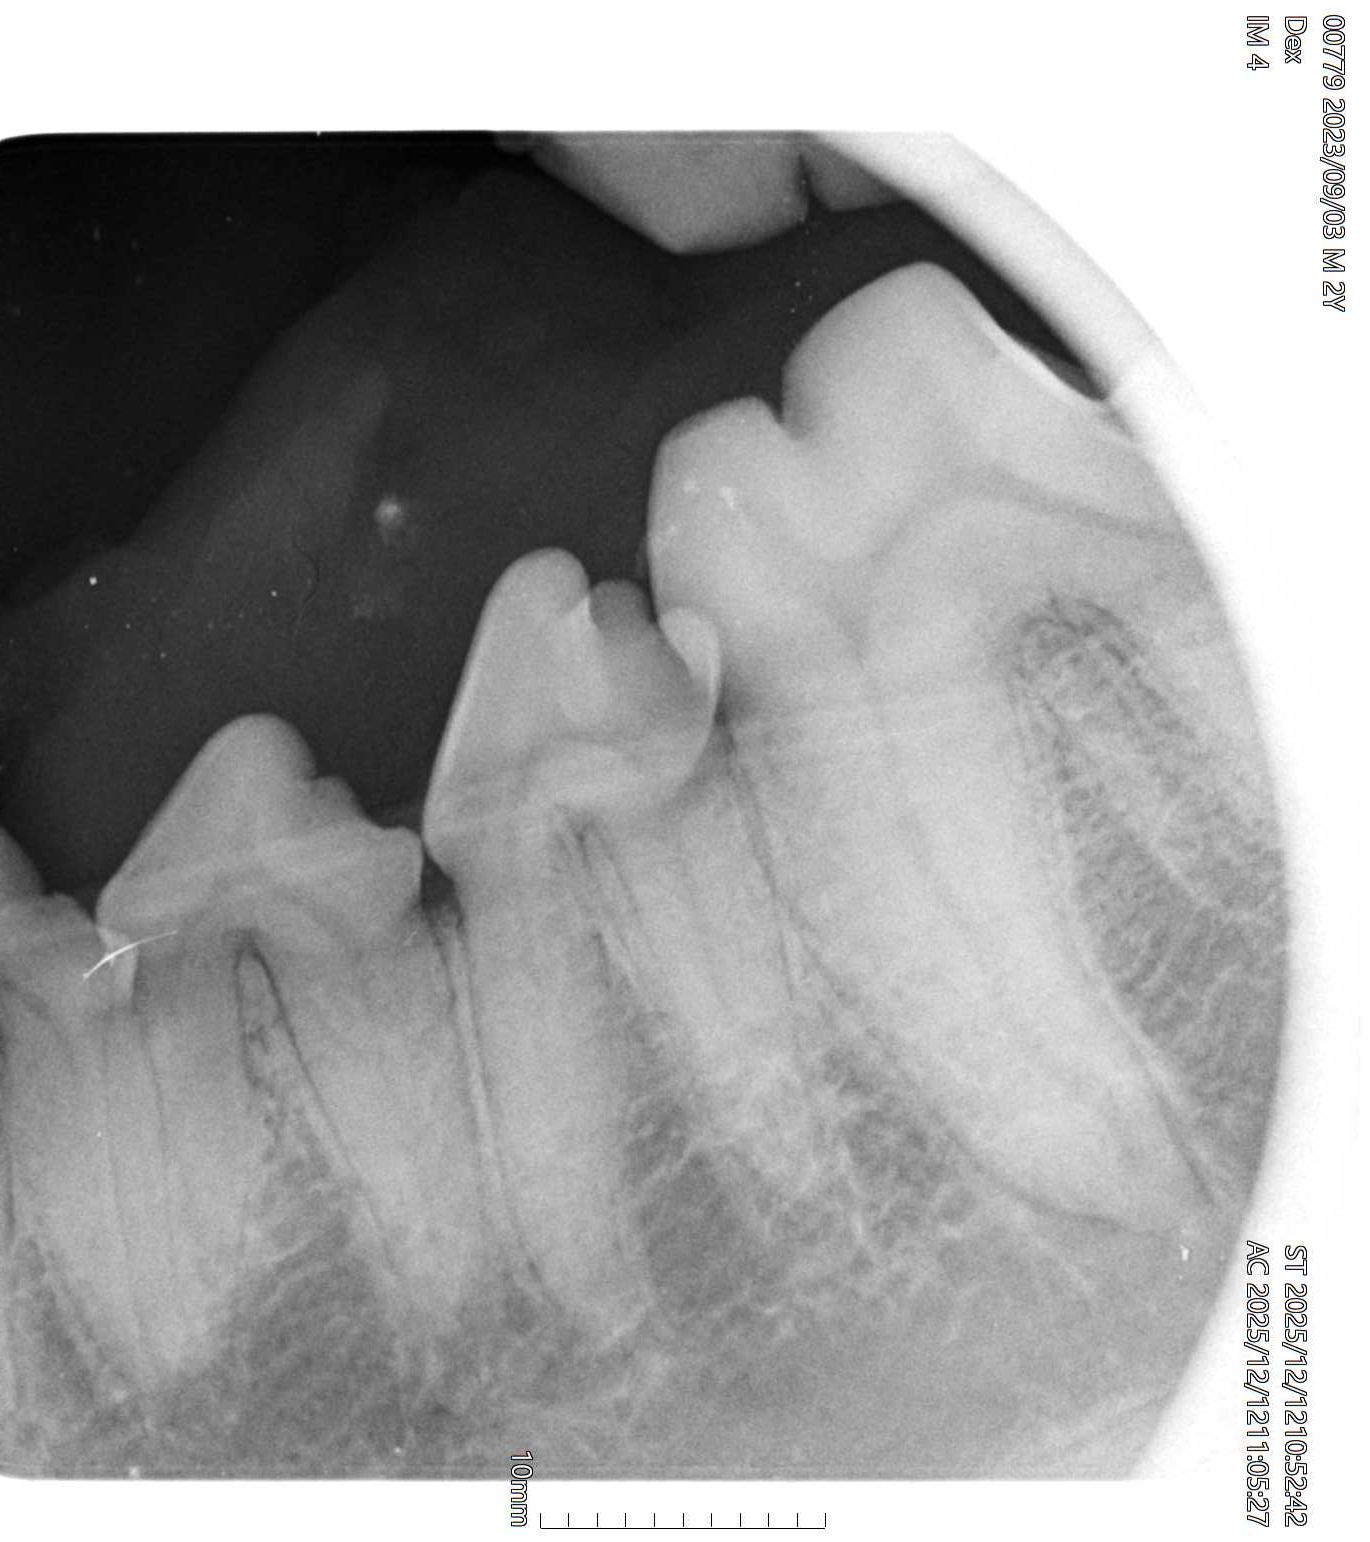

Sinds kort is Dierenkliniek Schinnen in bezit van de modernste tandheelkundige röntgen. Net als bij de tandarts worden plaatjes in de mond gedaan om te kijken of er kiezen of tanden aan het ontsteken zijn.

65 procent van de volwassen honden heeft een of meerdere beginnende of gevorderde ontstekingen van tanden en kiezen. Ze kunnen het alleen niet zeggen. En honden en katten laten het niet snel blijken.

We krijgen goed pas zicht op de staat van het gebit als onder verdoving het tandsteen is verwijderd. Hierna wordt gekeken met een sonde of er te veel ruimte tussen kies en tandkas is. Als dat het geval is dan is zo een wortel verdacht en kunnen we een foto maken om te kijken of we de kies kunnen laten zitten of dat de kies toch getrokken moet worden.